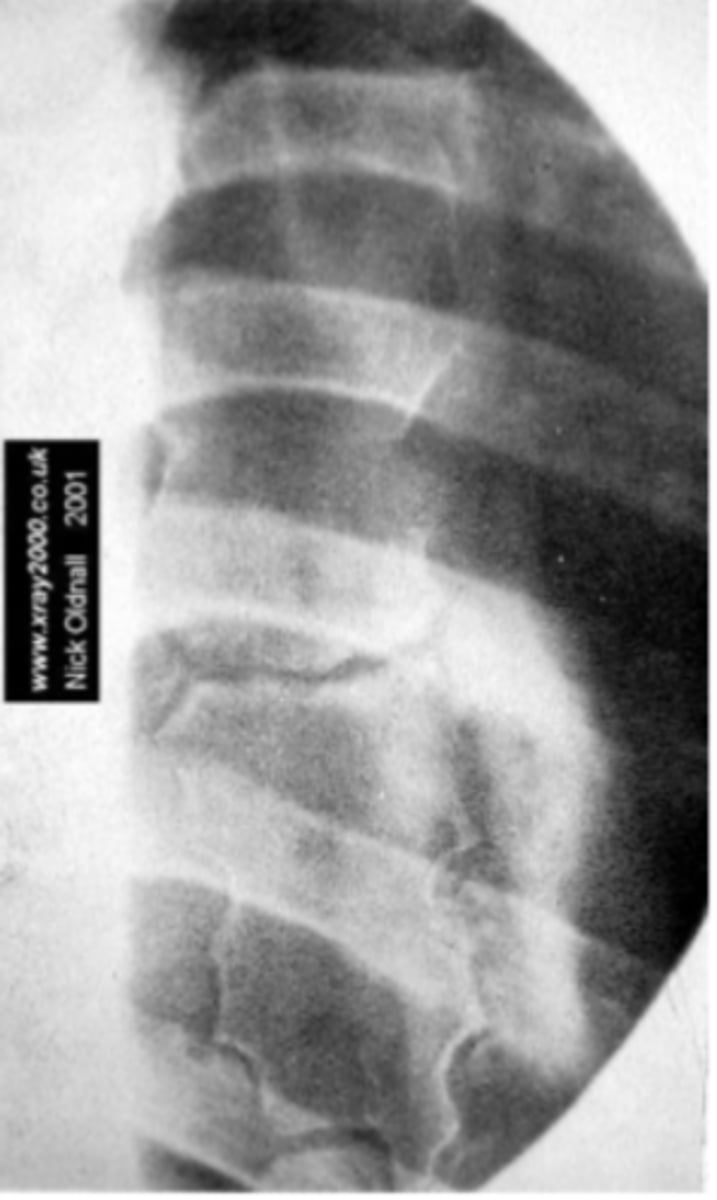

Lateral Lspine

What view is this?